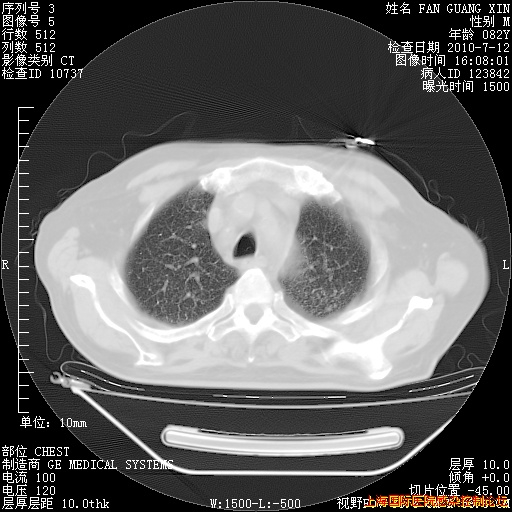

补发6月12日肺部CT肺窗

6月12日肺窗